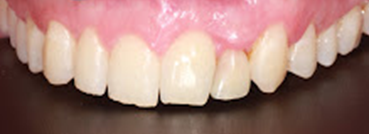

El objetivo del presente caso clínico es describir la colocación de un implante monobloque de circona para reponer un incisivo lateral superior izquierdo en un paciente de 34 años de edad, para la posterior realización de una corona implantosoportada monolítica de circona.

El objetivo del presente caso clínico es describir la colocación de un implante de circona para reponer un incisivo lateral superior izquierdo en un paciente de 34 años de edad, para la posterior realización de una corona implantosoportada monolítica de circona.